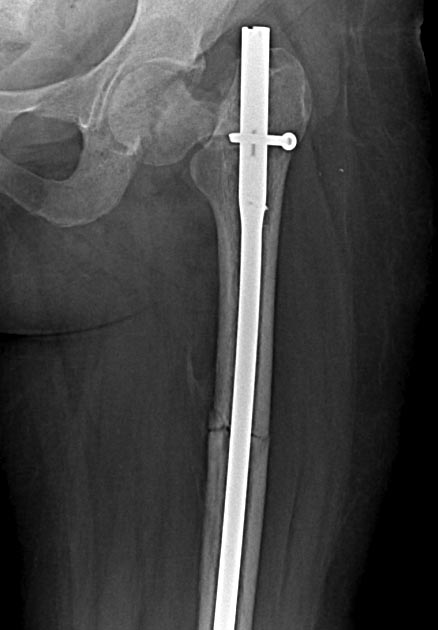

Две несросшихся шейки бедра, пацинтка 27 лет, травме 5 месяцев

БИОС плеча, Чкдо на л/запястный сустав, Биос левого бедра, Мос правой шейки бедра винтами.

Причина обращения -выявленный ложный сустав шейки левого бедра. При дообследовании выявлен несросшийся перелом шейки бедра на винтах.

Опороспособность обеих н/конечностей резко снижена, может стоять на правой, передвигается на каляске.Что думаем: слева однозначно протез, но бедро не срослось, менять гвоздь на пластину, пластина или которкая, или опасность конфликта с ножкой протеза, можно подождать консолидации и разбираться с правой конечностью.Справа остесинтез с коррегирующей остеотомией, но смущает состояние верхнего полюса после миграции винтов, что может повлечь протезирование на фоне нарушения анатомии проксимального бедра, что не хорошо для выживаемости протеза у 27 летней пациентки. Может сразу протез ?КТ головки не информативна из-за винтов